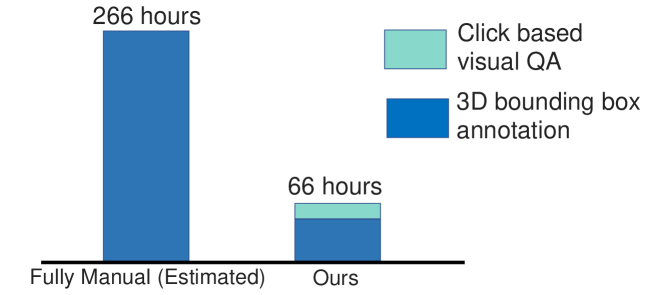

Ideally we would possess as large a dataset as possible of \acCT volumes, all with bounding-box-labeled primary lesions. More typically though, one would only possess a small cohort of fully-labeled patient data, , where and denote the image-level label of lesion type and bounding box or mask labels, respectively. It also typically possible to obtain an even larger cohort of patient data with only image-level labels, e.g. data mined from hospital archives. We denote the weakly labelled data , where . Based on our calculations, annotating 3D liver lesion bounding boxes consumes roughly minutes per \acCT study (Fig. 7) by a board-certified physician, making it prohibitive to completely annotate all patient studies. Therefore we wish to develop scalable weakly supervised learning and data curation methods to deal with any large-scale dataset.

Since only Patho-200 has localizations, we use the data curation pipeline of Sec. II-B to extract tumor \acpROI from Patho-1000. The labor savings () provided by the curation is presented in Fig. 7. In total, this required employing our mouse-click \acQA on lesion candidates ( min/study) and executing 3D bounding box annotations ( min/study) on 193 patients whose primary tumors were not captured by the proposals. Our test set consists of patients ( multi-phase CT scans), which were fully annotated by our collaborating physician with years of experience. This population is comparable or larger than previous studies [12, 11, 10].